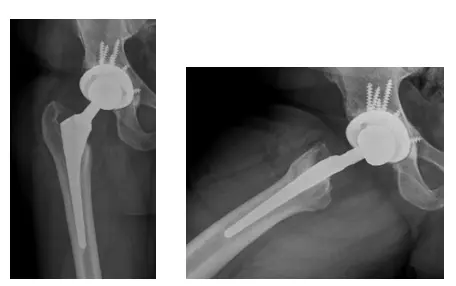

El Sr. JF es un caballero de 83 años que se había sometido previamente a un reemplazo total de cadera en otra institución aproximadamente 13 años antes de ser remitido a mí. Al principio se recuperó bien de la intervención y había estado asintomático durante gran...

El paciente es un varón de 70 años que acudió con dolor intenso en la cadera izquierda tras haberse sometido a una artroplastia total de cadera izquierda (ATC) hace varios años. En la visita inicial, las radiografías mostraban signos de osteólisis periprotésica del...

La paciente es una mujer de 50 años que acudió con dolor agudo en la cadera izquierda desde que se le practicó una artroplastia total de cadera izquierda (ATC) hace dos años en un centro externo. La paciente declaró que también tenía antecedentes de artrosis en la...

El paciente es un varón de 70 años que acudió quejándose de dolor en la cadera derecha. Había declarado que sufría este dolor desde hacía unos años y que había ido empeorando. Había informado de que le habían realizado una artroplastia total de cadera derecha (ATC)...

El paciente es un varón de 80 años con antecedentes de cáncer de próstata, hipertensión y estenosis espinal. El paciente había acudido por primera vez a principios de 2013 quejándose de un dolor en la cadera derecha que venía padeciendo desde hacía unos años. Afirmó...

El paciente es un varón de 73 años que acudió con dolor en la cadera derecha. Tras revisar las radiografías, se determinó que el paciente tenía una fractura de cadera y una artritis degenerativa grave en la cadera derecha. Se aconsejó a la paciente que una...

La paciente es una mujer de 65 años que acudió aproximadamente un año después de someterse a una artroplastia total de cadera derecha y presentaba una fractura de fémur desplazada. El paciente necesitó un procedimiento de fijación interna de reducción abierta (ORIF)...

El paciente es un varón de 55 años que acudió a nosotros quejándose de luxación recurrente de prótesis de cadera derecha. El paciente declaró que esto había estado ocurriendo desde que tuvo una artroplastia total de cadera derecha (THA) hace unos años realizada en una...